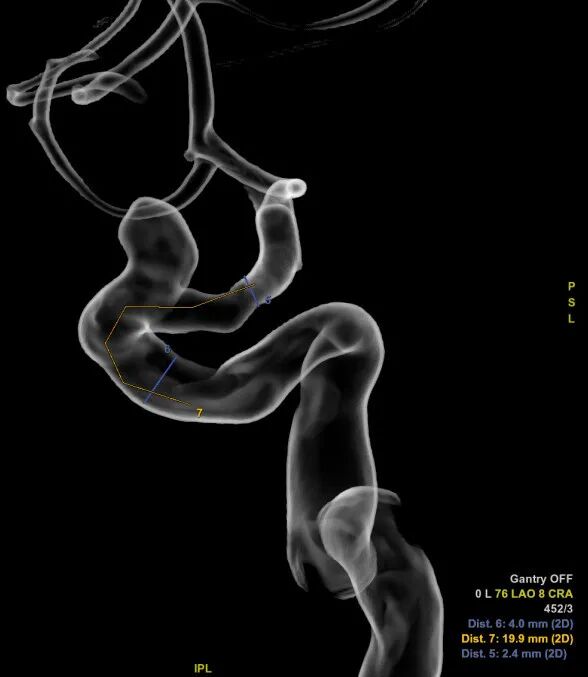

术前DSA造影:动脉瘤大小:4.9mm*4.8mm,动脉瘤颈:4.0mm;载瘤动脉远端直径:2.4mm,近端直径:4.0mm,长度:19.9mm。

DSA正位造影

动脉瘤大小测量

载瘤动脉测量